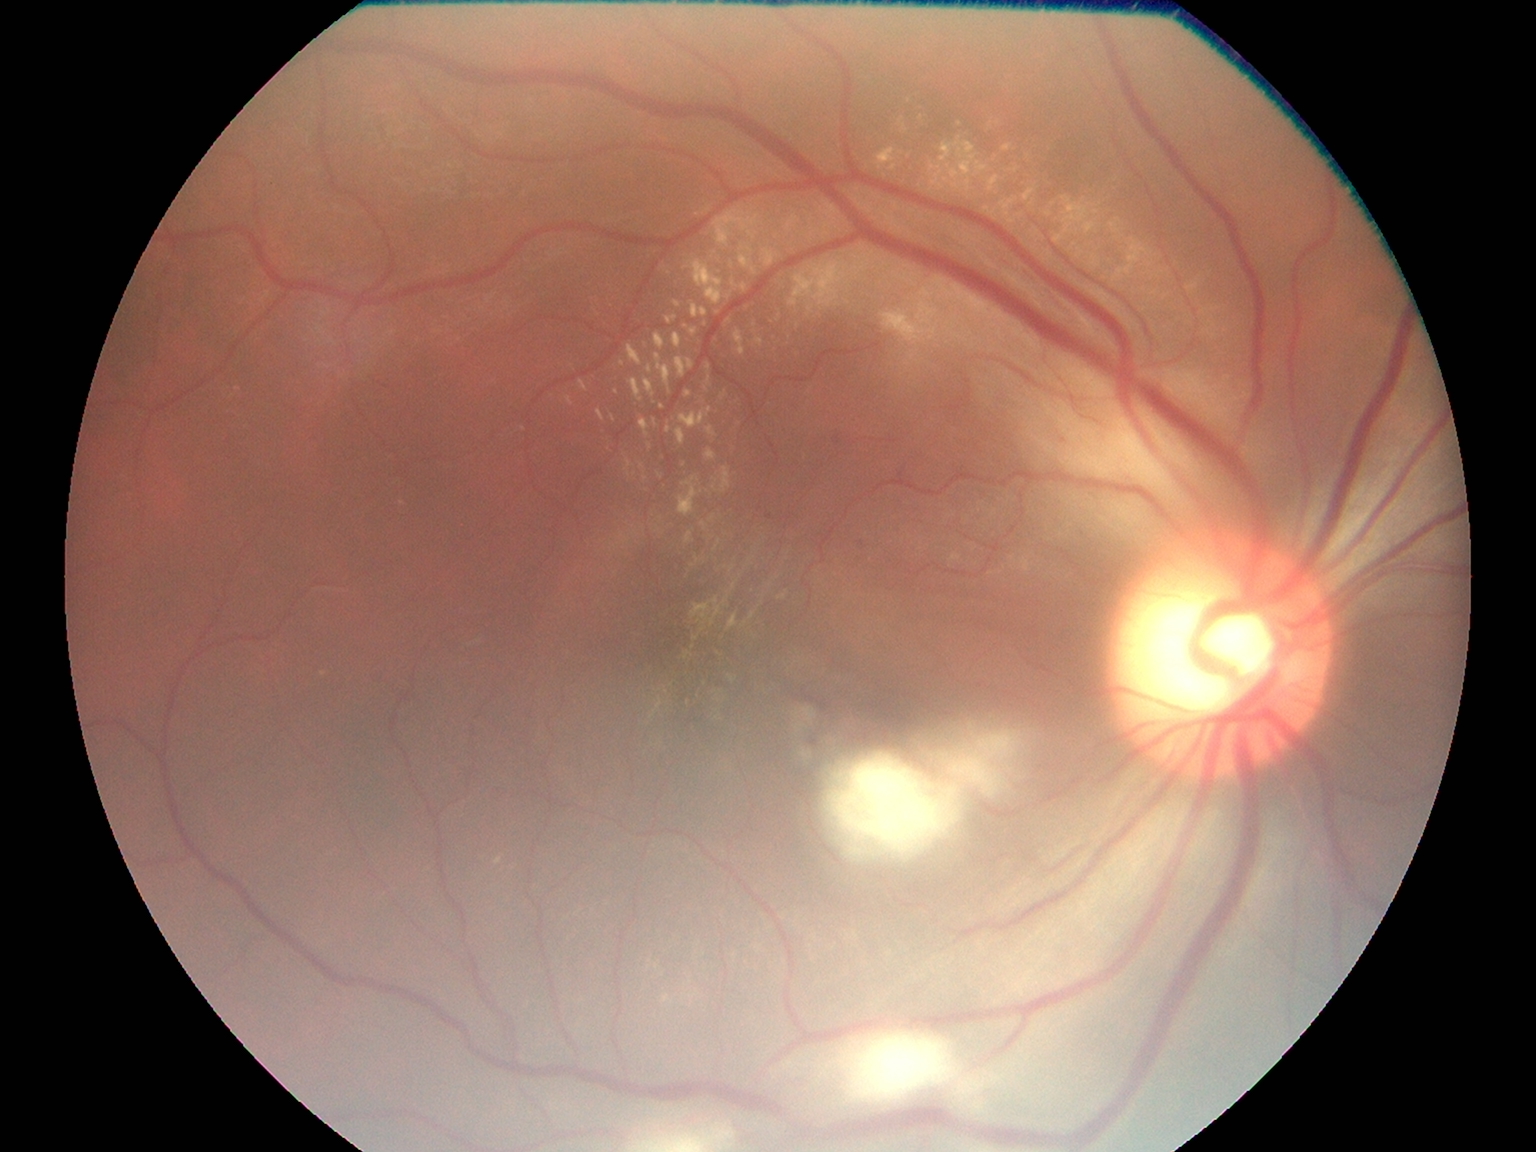

Top Retina Specialist

Advanced Retina Treatment